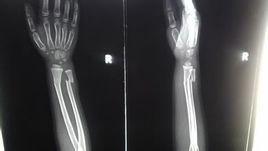

臨床檢查時,局部腫脹,骨折端壓痛,旋轉功能障礙。可聞及骨擦音。攝X線片時,應包括腕關節,注意有無下尺橈關節脫位。

橈骨單骨折,多可閉合復位,夾板或石膏固定。復位時按照以遠端對近端原則,根據骨折的不同位置,將遠折段牽開再行糾正旋轉移位。骨折整復後,於透視下判斷橈骨骨折間穩定後,行中立位夾板或石膏固定。如骨折間穩定性差時,固定位置以近折段的旋轉方位為準。

橈骨幹中下段或中下1/3段骨折,因其周圍軟組織相對較薄,多可通過閉合復位治療。若移位較多,不能復位者可考慮行切開整復鋼板固定。如鋼板固定可靠,術後不用外固定,早期進行功能鍛鍊。